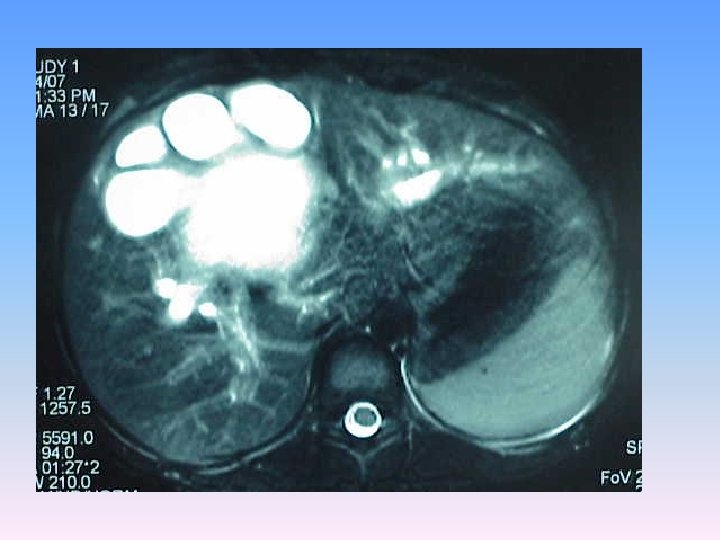

MRCP & MRI § Huge thicked wall cystic mass (140 x 120 mm), at the portahepatis that seems connected to biliary tree and gall bladder, resulted in severe dilatation of intra hepatic bile ducts and displaced right kidney posteriorly. § Spleen, kidneys, bowel loops and abdominal wall are normal. § Finding could be due to congenital anomalies like choledocal cyst, Duplication cyst, mesenteric cyst and hydatid cyst are in DDx.